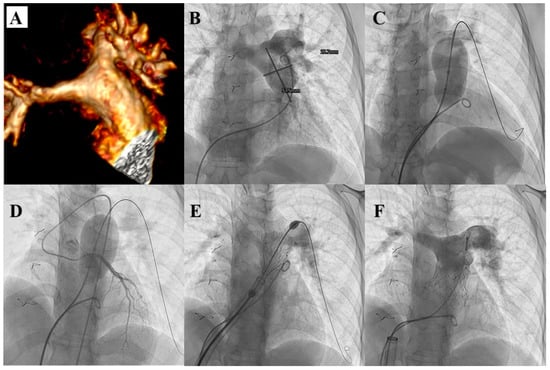

- D’Aiello, A.F.; Schianchi, L.; Bevilacqua, F.; Ferrero, P.; Micheletti, A.; Negura, D.G.; Pasqualin, G.; Chessa, M. Holography-guided procedural planning for modifying Venus P-Valve implantation technique in patients with left pulmonary artery stents: A case-series. Front. Cardiovasc. Med. 2024, 11, 1378924. [Google Scholar] [CrossRef]

- Zablah, J.E.; Than, J.; Browne, L.P.; Rodriguez, S.; Morgan, G.J. Patient Screening for Self-Expanding Percutaneous Pulmonary Valves Using Virtual Reality. J. Am. Heart Assoc. 2024, 13, e033239. [Google Scholar] [CrossRef]

- Garay, F.; Pan, X.; Zhang, Y.J.; Wang, C.; Springmuller, D. Early experience with the Venus P-Valve for percutaneous pulmonary valve implantation in native outflow tract. Neth. Heart J. 2017, 25, 76–81. [Google Scholar] [CrossRef] [PubMed]

- Morgan, G.; Prachasilchai, P.; Promphan, W.; Rosenthal, E.; Sivakumar, K.; Kappanayil, M.; Sakidjan, I.; Walsh, K.P.; Kenny, D.; Thomson, J.; et al. Medium-term results of percutaneous pulmonary valve implantation using the Venus P-Valve: International experience. EuroIntervention 2019, 14, 1363–1370. [Google Scholar] [CrossRef] [PubMed]

- Jin, Q.; Long, Y.; Zhang, G.; Pan, X.; Chen, M.; Feng, Y.; Liu, J.; Yu, S.; Pan, W.; Zhou, D.; et al. Five-year follow-up after percutaneous pulmonary valve implantation using the Venus P-Valve system for patients with pulmonary regurgitation and an enlarged native right ventricular outflow tract. Catheter. Cardiovasc. Interv. 2024, 103, 359–366. [Google Scholar] [CrossRef]